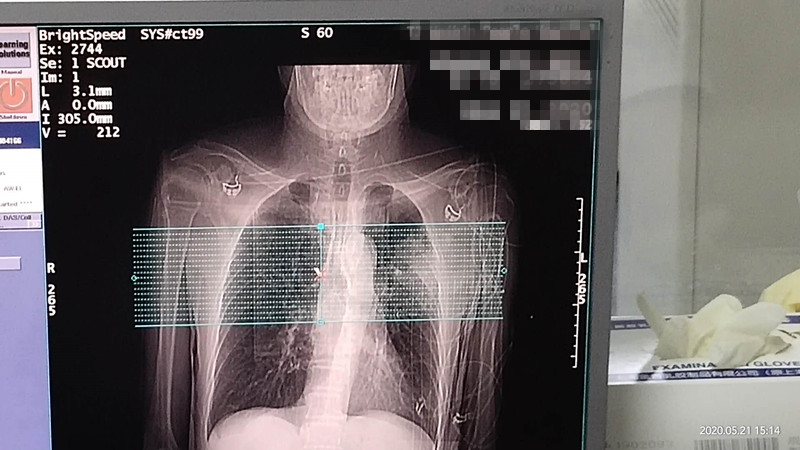

76岁肺部氩氦刀冷冻消融

发布人:美国氩氦刀技术官方网站    发布时间:2020/5/22 15:12:45